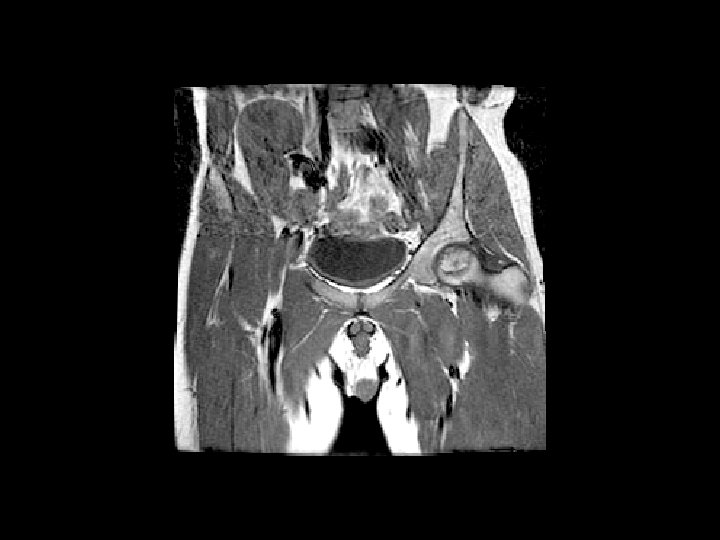

Femoral Head AVN • Findings: – bilateral femoral head AVN w/o collapse – right pelvic renal tx